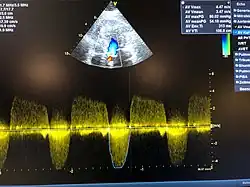

Aortenklappenstenose

Die Aortenklappenstenose, meistens verkürzt Aortenstenose genannt, ist eine angeborene oder erworbene Einengung des Ausflusstraktes der linken Herzkammer und gehört zu den häufigsten primären Herzklappenerkrankungen.

Angina pectoris, Synkope und Dyspnoe sind bei Aortenstenose wichtige Leitsymptome, die vor allem bei Belastung[2] und bei einer Öffnungsfläche der Aortenklappe von unter 0,8 cm² auftreten können. Ein Anstieg der Herzfrequenz führt zu einem Abfall des Schlagvolumens, aber tendenziell zu einer Zunahme des Herzzeitvolumens.[3] Weitere Symptome sind eine blasse Gesichtsfarbe und ein niedriger Blutdruck mit verkleinerter Amplitude (Pulsdruck). Bei der Auskultation des Brustkorbs über dem Herzen ist ein meist lautes (bei der Phonokardiographie auch „spindelförmiges“) systolisches Geräusch, das nach dem häufig abgeschwächten 1. und vor dem meist ebenfalls abgeschwächten 2. Herzton auftritt, bis über der Aortenregion bis zu den Karotiden fortgeleitet wahrzunehmen. Öfter ist auch ein 4. Ton als Extraton zu hören.[4]